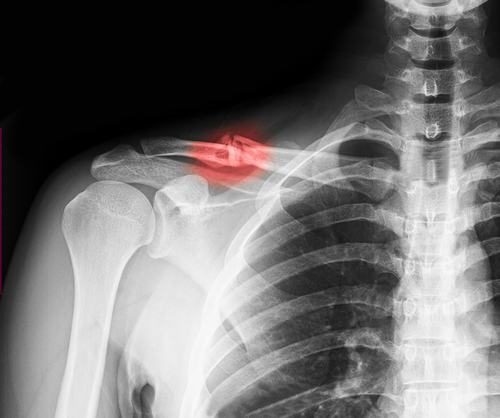

Xương đòn là xương nằm dài nằm dưới da vùng vai, nối giữa xương ức cùng hệ thống đai vai – cánh tay. Xương đòn có tác dụng như thanh chống giữa thân mình và khớp vai, giúp khớp vai hoạt động. Xương đòn còn có chức năng bảo vệ các cấu trúc quan trọng như phổi, bó mạch dưới đòn, đám rối cánh tay…

Gãy xương đòn (hay còn gọi là xương quai xanh) là tổn thương sau tai nạn trong sinh hoạt, chơi thể thao hoặc tai nạn giao thông. Gãy xương đòn chiếm khoảng 2,6% trong các trường hợp gãy xương Đối tượng có nguy cơ cao là trẻ em và người trẻ tuổi. Đây là những người thường xuyên hoạt động mạnh, nhanh, với cường độ cao.

Xương đòn gãy không quá nguy hiểm và khá nhanh lành do xương đón có màng xương dày, lại nằm tại vị trí lồng ngực, được cung cấp nguồn máu dồi dào. Tuy nhiên, một số trường hợp gãy xương phức tạp hơn do chấn thương hoặc tai nạn nghiệm trọng.

Các mảnh xương gãy có thể đâm vào các bó thần kinh hay mạch máu quan trọng nằm dưới xương đòn, đám rối cánh tay hoặc đâm vào phổi gây tràn khí, tràn máu màng phổi, đe dọa tới tính mạng người bệnh.